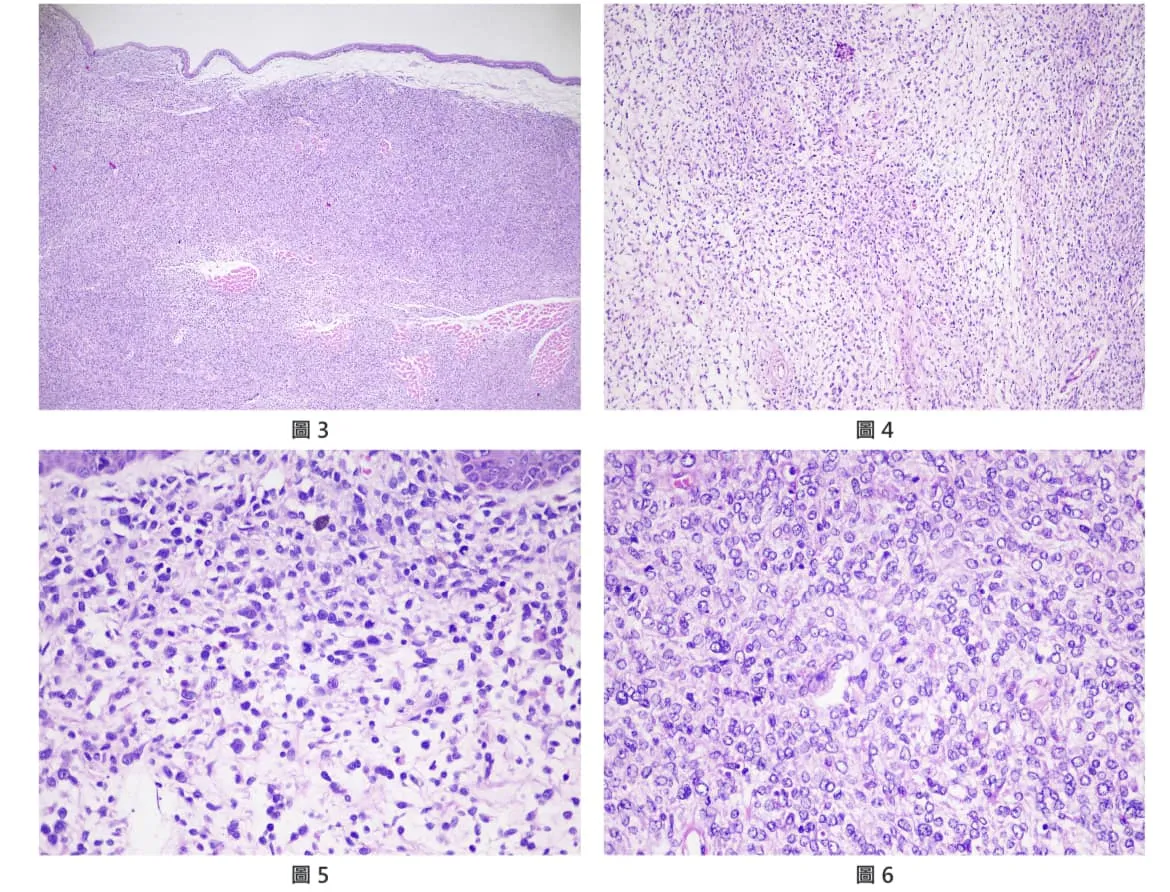

復發的黑色素瘤,具有一定的侵犯性,保守切除極易復發。

切除下來的腫瘤,需要進行病理化驗以確保切除邊緣沒有腫瘤殘留

切片確診為惡性黑色素瘤,然而手術邊界完整,已經可以大幅降低原位復發之機率。